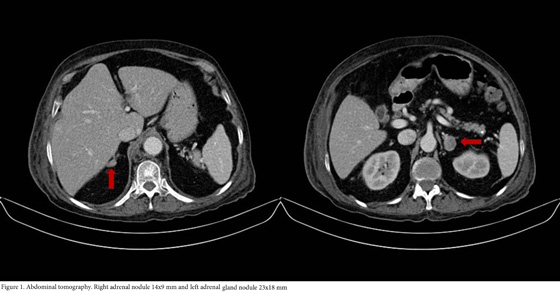

A 76 years-old woman with history of controlled hypertension (with losartan and amlodipine) presented to our hospital referring weight loss of 4 kg in two months, edema that progressed to anasarca and back lumbar pain. Besides the edema her physical examination was completely normal with no clinical signs suggestive of hypercortisolism. Among the studies requested, an abdominal tomography showed a right adrenal gland nodule of 14x9 mm and another one in the left adrenal gland of 23x18 mm (Fig. 1), additionally multiple vertebral fractures were reported. As part of the study of adrenal adenomas the patient had an abnormal value of cortisol after a low dose suppression test with dexamethasone (13.3 µg/dL (normal value: <1.8 µg/dL), with a normal value of free urinary cortisol and her potassium was low (she was not on diuretics). The results of the patient laboratory test are shown on Table 1.